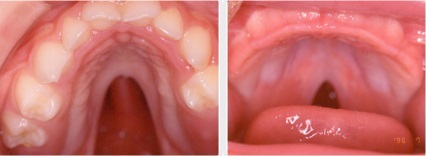

b) Características orales asociadas al Síndrome de Pierre Robin:

• Paladar alto, arqueado y fisurado.